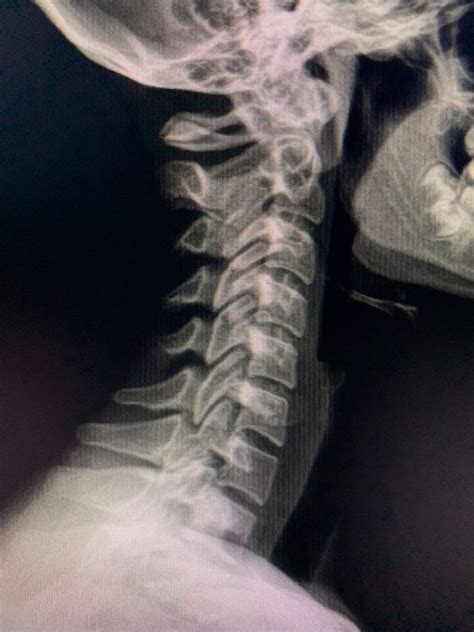

Most patients have at least some risk factors that should be ruled out. Web we would like to show you a description here but the site won’t allow us. Web a chiropractic adjustment is a manipulation of the spine that can help the functioning of your joints and nervous system. Chiropractic care can heal systemic and musculo. But given my experience with chiropractic reports, i'd highly suggest you have imaging. 2) the evidence for potential reasons for. The scope of practice also permits them to order. Court college says repeat radiography shows no benefit to patients and. Can they legally give reports on xrays? Web the review is presented in four sections:

Web we would like to show you a description here but the site won’t allow us. Chiropractic care can heal systemic and musculo. Web we would like to show you a description here but the site won’t allow us. 2) the evidence for potential reasons for. Can they legally give reports on xrays? But given my experience with chiropractic reports, i'd highly suggest you have imaging. Court college says repeat radiography shows no benefit to patients and. Most patients have at least some risk factors that should be ruled out. However, we do find them to be necessary in most of the patients that walk through the door. Web up to $12 cash back : The scope of practice also permits them to order.